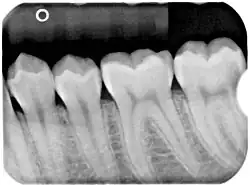

Panoramic(figure 1) and apical(figure 2) radiographs are commonly utilised in routine examinations to aid in the initial detection of BBC.[15] BBC is characterised by a well-defined radiolucent lesion on the buccal aspect of the tooth extending from furcation to the root apices.[19][20] With the presence of periosteal reaction on the buccal aspect of the tooth.[21][22] Tilting of the affected molars, with the apices of the roots tilted lingually and cusp tip buccally.[21][22] Unlike a periapical cyst, the periodontal ligament space and lamina dura remain intact and continuous, suggesting that the lesion is not directly associated with the root apices.[15][21][22]

As for the investigations, clinical and radiographic examinations are typically done. Clinically, the cyst often presents in children or teenagers with swelling on the buccal aspect of the mandibular molars, along with mild pain or infection.[13] The several radiographic imaging techniques that can be used include panoramic X-rays, periapical radiographs, and cone beam computed tomography.

Panoramic and periapical X-rays are usually performed first to identify the radiolucency on the buccal aspect of the tooth of interest, without involving the apex of the tooth.[13] The roots of the impacted tooth are usually bound by a well-defined radiolucent lesion.[13]